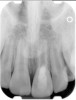

Clinical procedure: If apical bone loss is present (Figure 1) a collagen/gelatin sponge (eg, Gelfoam®, Pfizer Inc., www.pfizer.com) can be placed apically so that the MTA can be delivered to the desired working length. (Any other surgical resorbable sponge would also work, such as OraPlug® [Salvin Dental Specialties, www.salvin.com], Surgifoam® [Midwest Dental, www.mwdental.com], or Surgispon® [Aegis Lifesciences, www.surgispon.com]). This is done by taking a small piece (2 mm x 2 mm) of the resorbable sponge and pushing it down to and through the root apex with an endodontic file. Once this is done, MTA is packed down the canal with a custom-fitted cone. The clinician can use a rubber stopper on the gutta-percha cone to know the exact length of MTA placed in the apical third (Figure 2). Once the apical third is sealed with 3 mm to 5 mm of MTA, the remaining coronal canal space can be back-filled using a warm gutta-percha technique (Figure 3).